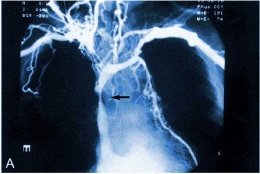

La evaluación inicial del paciente deberá incluir una radiografia de tórax para buscar masas mediastínicas y condiciones relacionadas como derrame pleural, colapso lobular o cardiomegalia. La exploración del tórax por tomografía computarizada (TAC) ofrece la información diagnóstica más útil y puede definir la anatomía de los ganglios mediastínicos afectados. La apertura venosa y la presencia de trombos se determinan usando contraste y técnicas rápidas de exploración. Dependiendo de la pericia local, la venografía de contraste o nuclear, las imágenes por resonancia magnética y la ecografía pueden ser valiosas para determinar el sitio y la naturaleza de la obstrucción.

Las limitaciones de la quimioterapia y de la radioterapia para el tratamiento de los tumores malignos relacionados con el síndrome de vena cava superior hacen optar por tratamientos paliativos. Si los síntomas son graves, se planteará la desobstrucción de la vena cava. Para ello, las técnicas endoluminales ofrecen grandes ventajas con mínimos riesgos. La fibrinólisis, si existe trombo sobreañadido, seguida de una angioplastia y aplicación de una endoprótesis (stent).